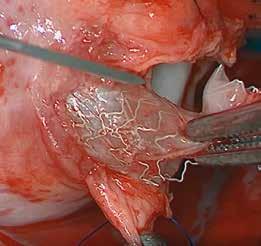

urVena is advancing coronary artery bypass grafting (CABG) with its novel PTP technology, a point-of-care therapy designed to strengthen venous tissue and dramatically improve long-term vein graft durability. Despite advances in surgical techniques and medical management, CABG's efficacy remains limited primarily due to vein graft failure and the progression of atherosclerosis in native coronary arteries. Vein graft failure is ascribed to the luminal narrowing that results from intimal hyperplasia, medial thickening, and subsequent concomitant accelerated atherosclerosis. Structurally, veins are not designed to withstand arterial pressure. Vein grafts excessively expand under arterial pressure, causing irreversible injury and progressive endothelial remodeling. Vein grafts are subject to reported degeneration and occlusion rates from 20-40% in the first year and as high as 50% at five years. SVG failure is associated with a significant increase in major adverse cardiovascular events (MACE), including death, myocardial infarction (MI), and the need for repeat revascularization.

DurVena’s PTP device addresses this challenge by applying Rose Bengal dye, a photo-initiator with a long history of medical use, to the exterior of the harvested vein. The coated vein is then exposed to LED light, which activates the dye, thereby creating additional collagen crosslinks in the extracellular matrix of the vein's adventitia. The collagen crosslinks increase tissue strength and decrease elasticity without altering the histological makeup of the vein. In extensive, published pre-clinical testing of PTP in both small and large animals, a significant increase in vein stiffness (5-fold), a comparable reduction in vein expansion, and a reduction in intimal hyperplasia (a precursor to stenosis and graft failure) have been demonstrated. In addition, Durvena has also completed a first-in-human safety study demonstrating no device-related events at 30 days, 6 months, and one year.

PTP therapy is precise and localized. Rose Bengal binds non-covalently to collagen in the extracellular matrix. Upon illumination, it forms covalent crosslinks between collagen

molecules, reinforcing the tissue. The dye penetrates only about 100µm into the adventitia, forming a stable surface band. There is no change to the histological makeup of the vein. The entire process is monitored by validated software, ensuring consistent and safe application.

This novel therapy is licensed from Massachusetts General Hospital and is being developed by an accomplished team of business professionals with several successful exits and extensive experience in start-up medical device development in this market sector. Durvena has significant intellectual property protections with broad claims covering the PTP method and devices for vein graft preparation, as well as other applications, that have been issued around the world. PTP technology has broad utility applicable beyond CABG, which DurVena will explore after initial success in the CABG market. The company has received Breakthrough Designation from the FDA and expects to enroll the first patient in a US pivotal trial in the first half of 2026.

DurVena’s PTP therapy represents a paradigm shift in vein graft preparation, offering a simple and effective solution to a longstanding clinical challenge. For clinicians, it holds promise for improving patient outcomes. For strategic partners, it offers a differentiated, IP-protected platform with expansion potential across multiple medical applications.